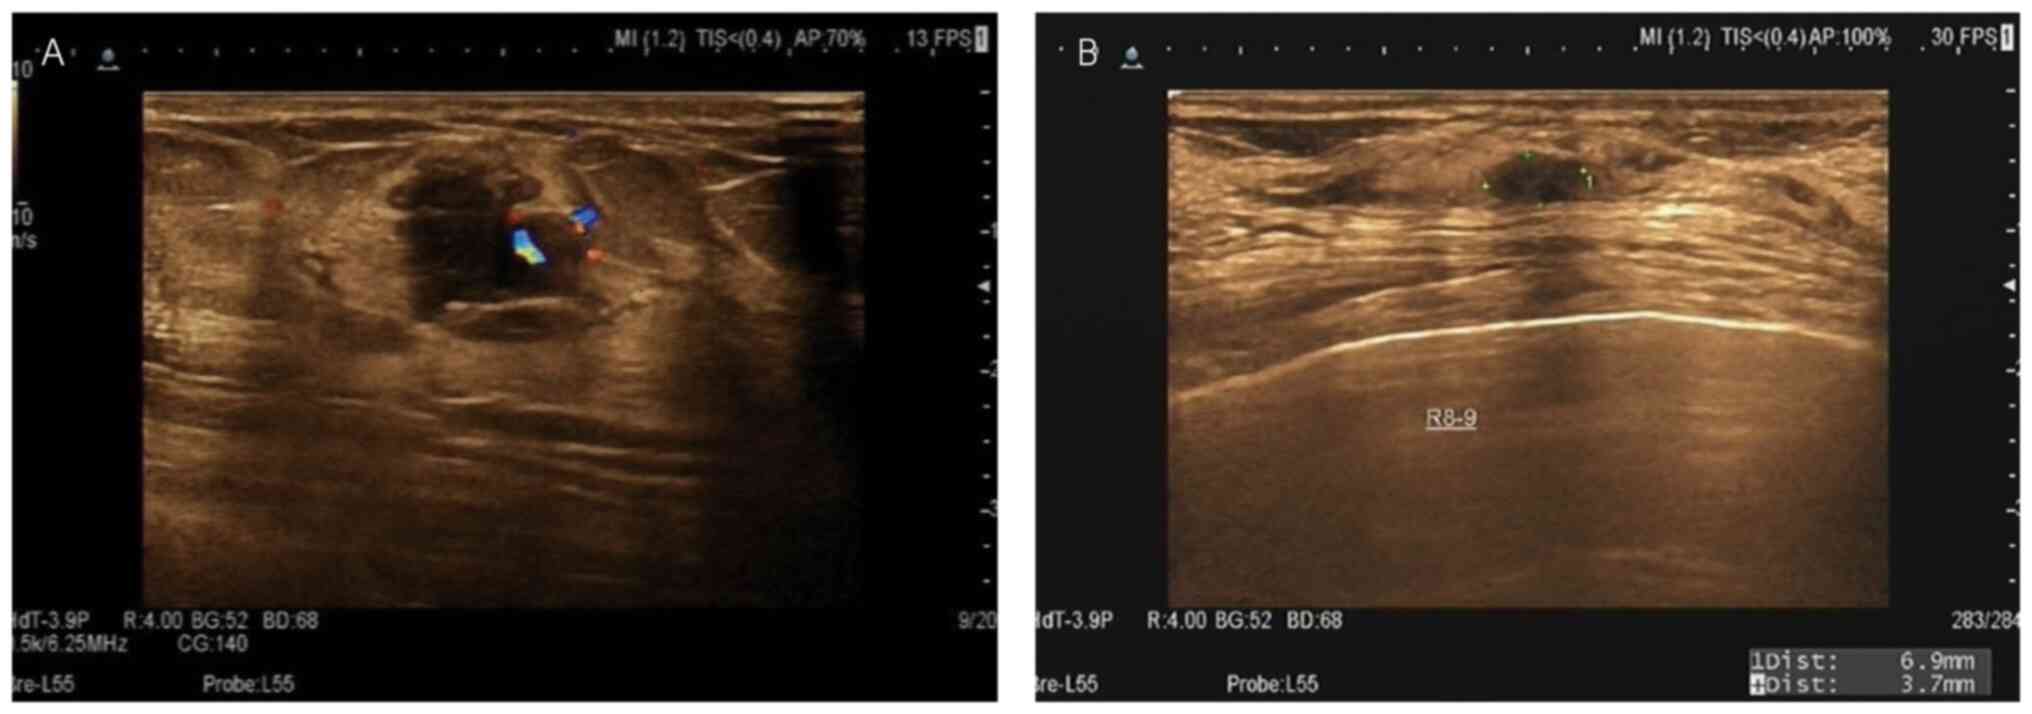

Although suspicious imaging descriptors are helpful in predicting breast cancer, their accuracy may be affected by age (14). Young patients with many suspicious imaging descriptors sometimes have false-positive results (27). By contrast, older patients may have malignant tumors with less suspicious imaging descriptors (Fig. 3).

Figure 3

Ultrasonography of young and old patients with Breast Imaging Reporting and Data System score 4B lesions. (A) A 35-year-old female patient with palpable breast mass, fuzzy boundary and blood flow signal, highly indicative of malignancy, was confirmed as fibroadenoma. (B) A 74-year-old female patient with few suspicious imaging descriptors, clear boundary and no angular margin, which was likely to be benign, was confirmed as invasive carcinoma.